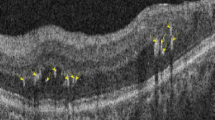

The patterns of false-positives on the segmented macular layers deviation maps were classified into 3 groups according to the shape and area of the abnormal color-coded area: group A (island shape circumpassing less than 180° in area) (Fig. 3a); group B (hook shape circumpassing more than 180° but less than 360° in area) (Fig. 3b); group C (donut shape around inner annulus, circumpassing 360° in area) (Fig. 3c). As for the determination of the false-positive-pattern groups, we found almost perfect interobserver agreement (kappa = 0.878 for GCL, 0.855 for IPL, and 0.891 for retinal layer, all ps < 0.001). Figure 4 reveals the true glaucomatous structural damage on the segmented macular layers and RNFL deviation maps.

False-positive patterns on deviation maps of segmented macular layers on Spectralis OCT. Each labeled row (a–c), from left to right, consists of a thickness map, a deviation map, a corresponding B-scan with colored lines demarcating the segmented layer, red-free retinal nerve fiber layer (RNFL) photography and Humphrey (Carl Zeiss Meditec, Dublin, CA, USA) C24–2 visual field. (a) Healthy eye of 58-year-old female with pattern group A (island shape circumpassing less than 180° in area) on ganglion cell layer (GCL) deviation map. (b) Healthy eye of 66-year-old female with pattern group B (hook shape circumpassing more than 180° but less than 360° in area) on inner plexiform layer (IPL) deviation map. (c) Healthy eye of 66-year-old female with pattern group C (donut shape around inner annulus, circumpassing 360° in area) on retinal layer deviation map.